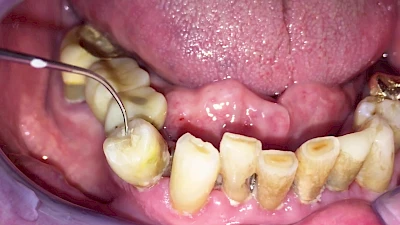

Eine geringe spürbare Beweglichkeit der Zähne ist durchaus normal, da Zähne über Fasern im Kieferknochen aufgehängt sind. Lassen sich Zähne, Kronen oder Brücken jedoch deutlich sichtbar bewegen, besteht die Gefahr, dass sie sich lösen und verschluckt oder aspiriert werden. Deshalb sollte in diesen Fällen der Zahnarzt verständigt werden.